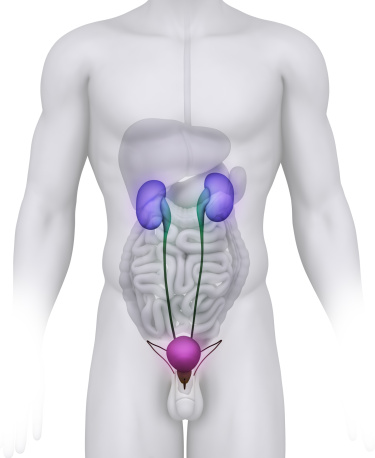

Overactive bladder syndrome is a condition that affects the storage function of your bladder and it leads to sudden, frequent and uncontrollable urges to urinate. In contrast to a healthy bladder, this condition can cause the urge to urinate when your bladder is not even close to full. If you have an overactive bladder, you may find it hard to suppress the urge to urinate and experience incontinence, which is an involuntary loss of urine. It is a rather common condition that affects approximately 15% of the overall population and 33% of the elderly population. Despite the fact that it is common, you may feel embarrassed by it and it can harm your mental health and wellbeing in a variety of ways if you do not actively seek treatment for it.